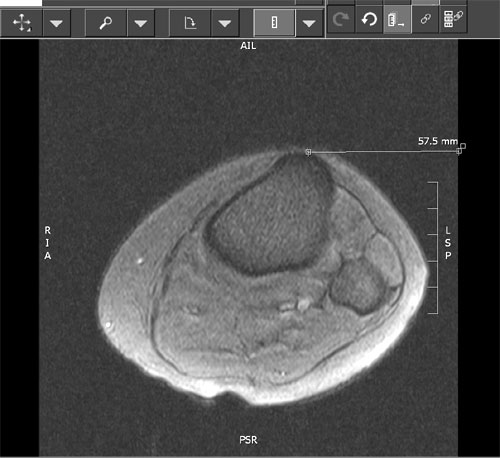

Måling af TTTG afstand (TTTG=Tuberositas Tibia Trochlea

Grove) er en mere præcis måling af Q-vinkel og malalignment:

Brug MR sagitale snit, kør ned til tuberositas og mål afstand fra midten af

tuberositas til kanten af billedet på skærmen. Gentag målingen fra midten af

troclea og træk de to tal fra hinanden. (Målet i eksemplet er 15,3 mm)